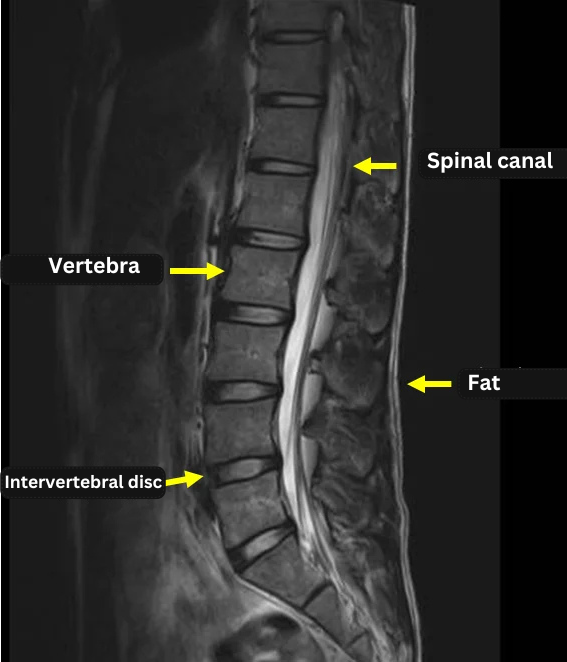

By examining the images below, you can see how the contrast changes between sequences.

(All three images were taken in the sagittal plane.)

T1 Imaging: Vertebral bodies (containing fat) appear bright (white). Spinal fluid is dark.